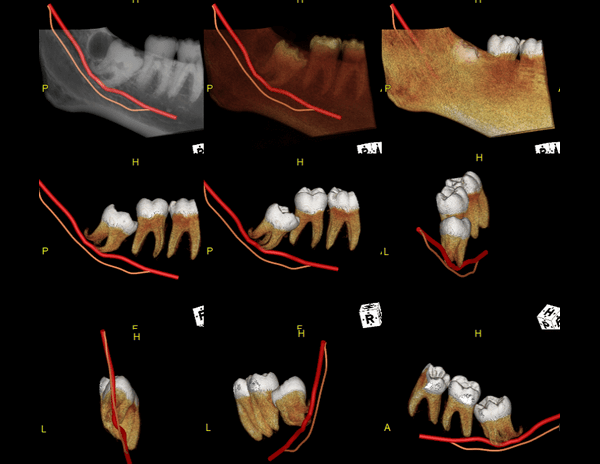

A Tomografia Computadorizada pela técnica do feixe cônico/cone beam (CBCT) introduziu um novo conceito de tomografia computadorizada na região bucomaxilofacial, que por meio da rápida aquisição volumétrica produz imagens com altíssimo grau de definição e fidelidade, além da redução na dose total de radiação emitida ao paciente.

Além disso, ocorre a minimização dos artefatos de imagem em relação à TC médica, o que torna possível a realização de imagens com qualidade diagnóstica e precisão sub-milimétrica, mesmo na presença de estruturas metálicas (restaurações, pinos/núcleos, aparelhos ortodônticos).